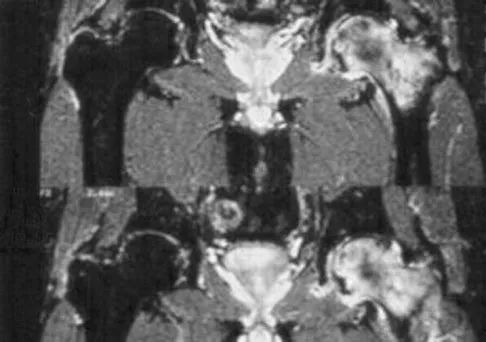

An 18-month-old boy with obstetric brachial plexus palsy is being evaluated for limited right shoulder motion. Physical therapy for the past 6 months has failed to result in improvement of the contracture. Which of the following studies is necessary prior to any shoulder reconstruction?